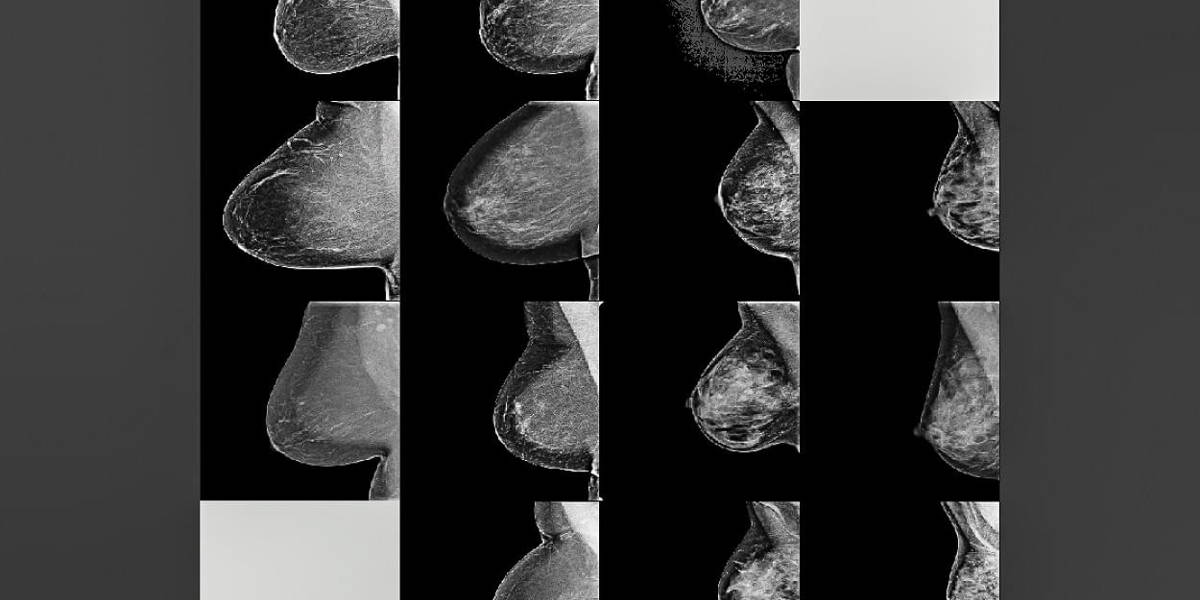

Each mammogram in the dataset has a standard Breast Imaging Reporting and Data System (BI-RADS) breast density rating in four categories: fatty, scattered (scattered density), heterogeneous (mostly dense), and dense. In both training and testing mammograms, about 40 percent were assessed as heterogeneous and dense.

During the training process, the model is given random mammograms to analyze. It learns to map the mammogram with expert radiologist density ratings. Dense breasts, for instance, contain glandular and fibrous connective tissue, which appear as compact networks of thick white lines and solid white patches. Fatty tissue networks appear much thinner, with gray area throughout. In testing, the model observes new mammograms and predicts the most likely density category.